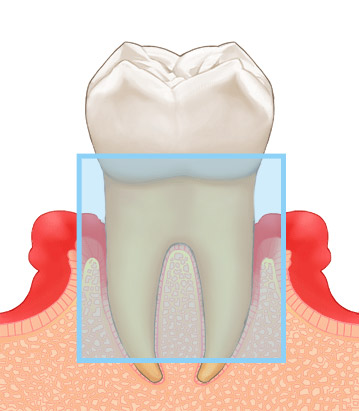

ここまで歯周病が進行するとGTR法が必要になります。

かなり歯槽骨の吸収がすすみ、歯の動きが感じられる様になり、膿がでて口臭が強くなります。